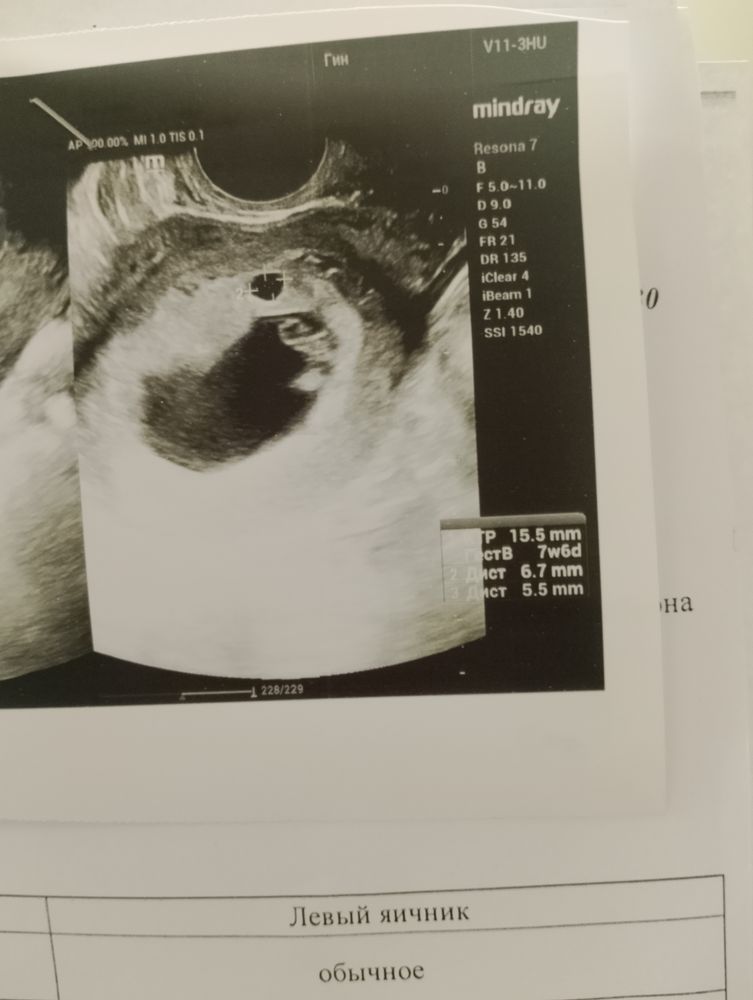

УЗИ, КТГ, доплер, скрининг, ХГЧ и другие анализыНа УЗИ ,9 января,врач сказал что кистозное образование ( УЗИ делала платно) на приёме у гинеколога задавала вопрос она молчит просто назначила ещё одно УЗИ на 22 января а я успокоиться не могу что это такое ( я сама из близнецов,и у бабушки двойни были )

Вероника Шевцова, по этому фото я бы не сказала что двойня , на снимке виду одно большое чёрное пятно , в нём эмбрион и желточный мешочек . И второе чёрное маленькое круглое , но оно же прям очень маленькое в сравнении с другим ... Поэтому не думаю что двойня

Верю в чудо, 7 недель по УЗИ первое УЗИ было в 3 недели было одно пя

Верю в чудо, я незнаю) написанно не киспа а именно кистообразное образование